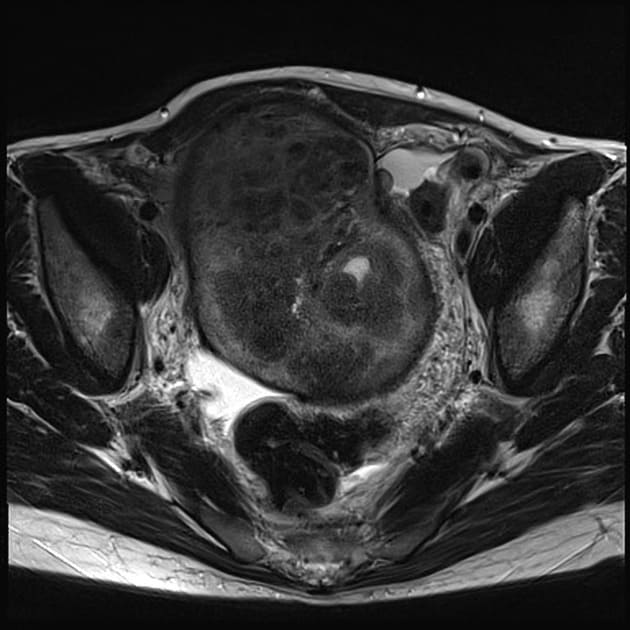

После МРТ органов малого таза врач-рентгенолог анализирует полученное изображение и дает заключение о выявленных патологиях. Если в ходе обследования обнаружены очаги эндометриоза, специалист отмечает их локализацию, стадию развития, патологические процессы и осложнения. Визуализируются 4 стадии эндометриоза при МРТ.

- Начальная стадия, для которой характерно небольшое утолщение стенок матки, изменения маточных труб, яичников. Благодаря тому, что томограф делает множественные снимки, толщина которых не превышает 1 мм, врач может увидеть малейшие отклонения показателей от нормы и определить поражение тканей эндометриоидными клетками.

- Вторая стадия характеризуется появлением мелких кист в мышечной ткани матки, яичниках.

- Третья стадия характеризуется утолщением стенок матки, мышечная структура органа становится неоднородной, четко визуализируются опухолевые очаги.

- Четвертая стадия является самой опасной для здоровья, т.к. патологический процесс может затрагивать влагалище, мочевой пузырь, кишечник и полость брюшины. МРТ фиксирует множественные кисты, узлы, спайки. Структура стенок органов малого таза визуализируется неоднородной, с многочисленными эндометриоидными включениями.

Врач-рентгенолог сравнивает полученные показатели с показателями нормы и выносит заключение о стадии развития эндометриоза. Гинеколог, изучив томограмму, сможет поставить правильный диагноз и исключить возможность злокачественной опухоли эндометрия матки.

Диагностика внутреннего эндометриоз на МРТ

Существует такое понятие как внутренний эндометриоз. Его называют аденомиоз. Характеризуется это заболевание проникновением в мышечный слой эндометрия. Такое заболевание дает о себе знать следующей симптоматикой: у женщины появляется ярко выраженная боль, которая усиливается во время менструации, выделения становятся более обильные, во время полового акта чувствуется дискомфорт или болевые ощущения. Причиной аденомеоза считается нарушение гормонального фона или наследственность. Диагностика внутреннего эндометриоза возможна с помощью УЗИ и МРТ органов малого таза. Томографию применяют в основном как дополнительный метод, когда аденомиоз сопряжен с опухолевым заболеванием или сильным разрастанием. На МРТ при внутреннем эндометриозе хорошо визуализируется увеличенная матка и в мышечном слое патологические изменения тканевого характера.

В последние годы ранняя диагностика эндометриоза шагнула вперед, в частности и благодаря тому, что выросли диагностические возможности УЗИ аппаратуры и в диагностическую практику гинеколог прочно вошла МРТ матки и яичников. Чтобы безошибочно диагностировать эндометриоз важно пройти обследование МРТ органов малого таза на высокопольном аппарате мощность не менее 1.5 Тесла. В ходе томографического исследования врач посмотрит важные параметры состояние матки, яичников и придатков. Во-первых, по данным томографии диагност оценит положение матки. В норме матка должна быть наклонена немного вперед, но бывают отклонения назад, что является особенностью женщины, а не патологией, но к сожалению, есть риск усложнения естественного процесса родов. Следующим важным параметром будут являться размеры матки. В норме ее длинна должна составлять 7 см, ширина 6 см, переднезадний 4,2 см. Меньшие размеры матки на МРТ укажут врачу на недоразвитие половых органов у женщины, а большие скажут о беременности или укажут на опухолевые процессы.

Неоднородные очаги стенок матки являются признаком патологии и могут свидетельствовать об эндометриозе или наличии полипа матки. В нормальном состоянии стенки матки имеют однородную структуру, а вот толщина может меняться с 5 мм до 20 мм. Это зависит от менструального цикла. В ходе МРТ малого таза врач измерит длину шейки матки, которая не должна превышать 4 см, переднезадний размер должен соответствовать 3 см. Параметры канала так же не должны превышать 3 мм. Увеличение размеров шейки матки на МРТ — это признак эндометриозе или опухоли. Затем по данным МРТ врач оценить маточные трубы и позадиматочное пространство, количество свободной жидкости, которое может иметь место только после процесса овуляции, в середине цикла. В завершении диагност пристально изучит состояние яичников и придатков с целью выявить возможные очаги эндометриоза яичников и увидеть признаки симптома “целующихся яичников”. Также в рамках МРТ малого таза у женщин проводится диагностика состояния брюшины и прямой кишки, чтобы исключить возможность эндометриоза брюшины.